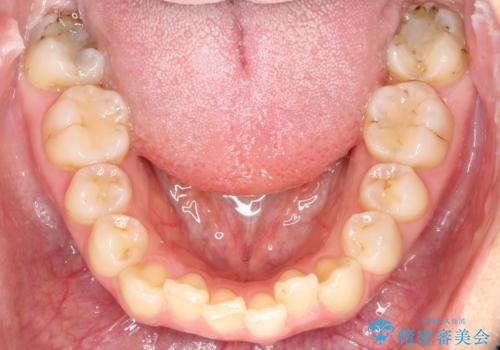

矯正後の後戻り インビザラインで改善

- 前歯のガタツキが気になると来院されました。

前歯のガタツキを改善する治療法として、マウスピース矯正が適していることが多いです。

マウスピース矯正は、金属製のブラケットやワイヤーを使用せずに、透明なマウスピースを装着して歯を移動させる方法です。そのため、目立たず、痛みも少ないです。